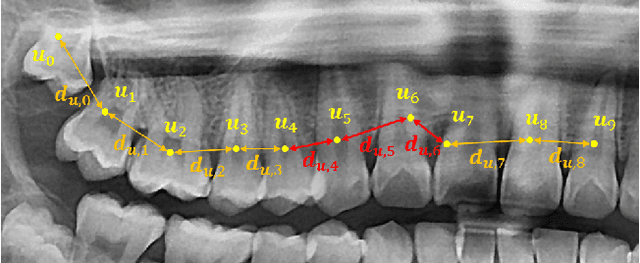

Abstract:Dental panoramic X-ray imaging is a popular diagnostic method owing to its very small dose of radiation. For an automated computer-aided diagnosis system in dental clinics, automatic detection and identification of individual teeth from panoramic X-ray images are critical prerequisites. In this study, we propose a point-wise tooth localization neural network by introducing a spatial distance regularization loss. The proposed network initially performs center point regression for all the anatomical teeth (i.e., 32 points), which automatically identifies each tooth. A novel distance regularization penalty is employed on the 32 points by considering $L_2$ regularization loss of Laplacian on spatial distances. Subsequently, teeth boxes are individually localized using a cascaded neural network on a patch basis. A multitask offset training is employed on the final output to improve the localization accuracy. Our method successfully localizes not only the existing teeth but also missing teeth; consequently, highly accurate detection and identification are achieved. The experimental results demonstrate that the proposed algorithm outperforms state-of-the-art approaches by increasing the average precision of teeth detection by 15.71% compared to the best performing method. The accuracy of identification achieved a precision of 0.997 and recall value of 0.972. Moreover, the proposed network does not require any additional identification algorithm owing to the preceding regression of the fixed 32 points regardless of the existence of the teeth.